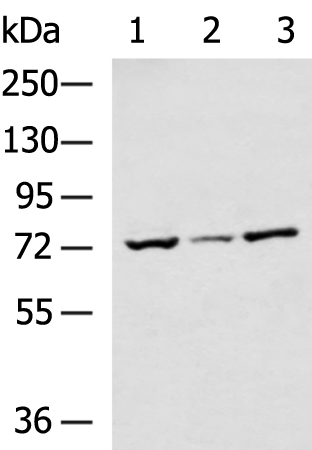

分类: 科研抗体货号: P10601别名: FSP1; GBP3; SPG3; HSN1D; SPG3A; AD-FSP; atlastin1应用: WB反应种属: Human, Mouse, Rat